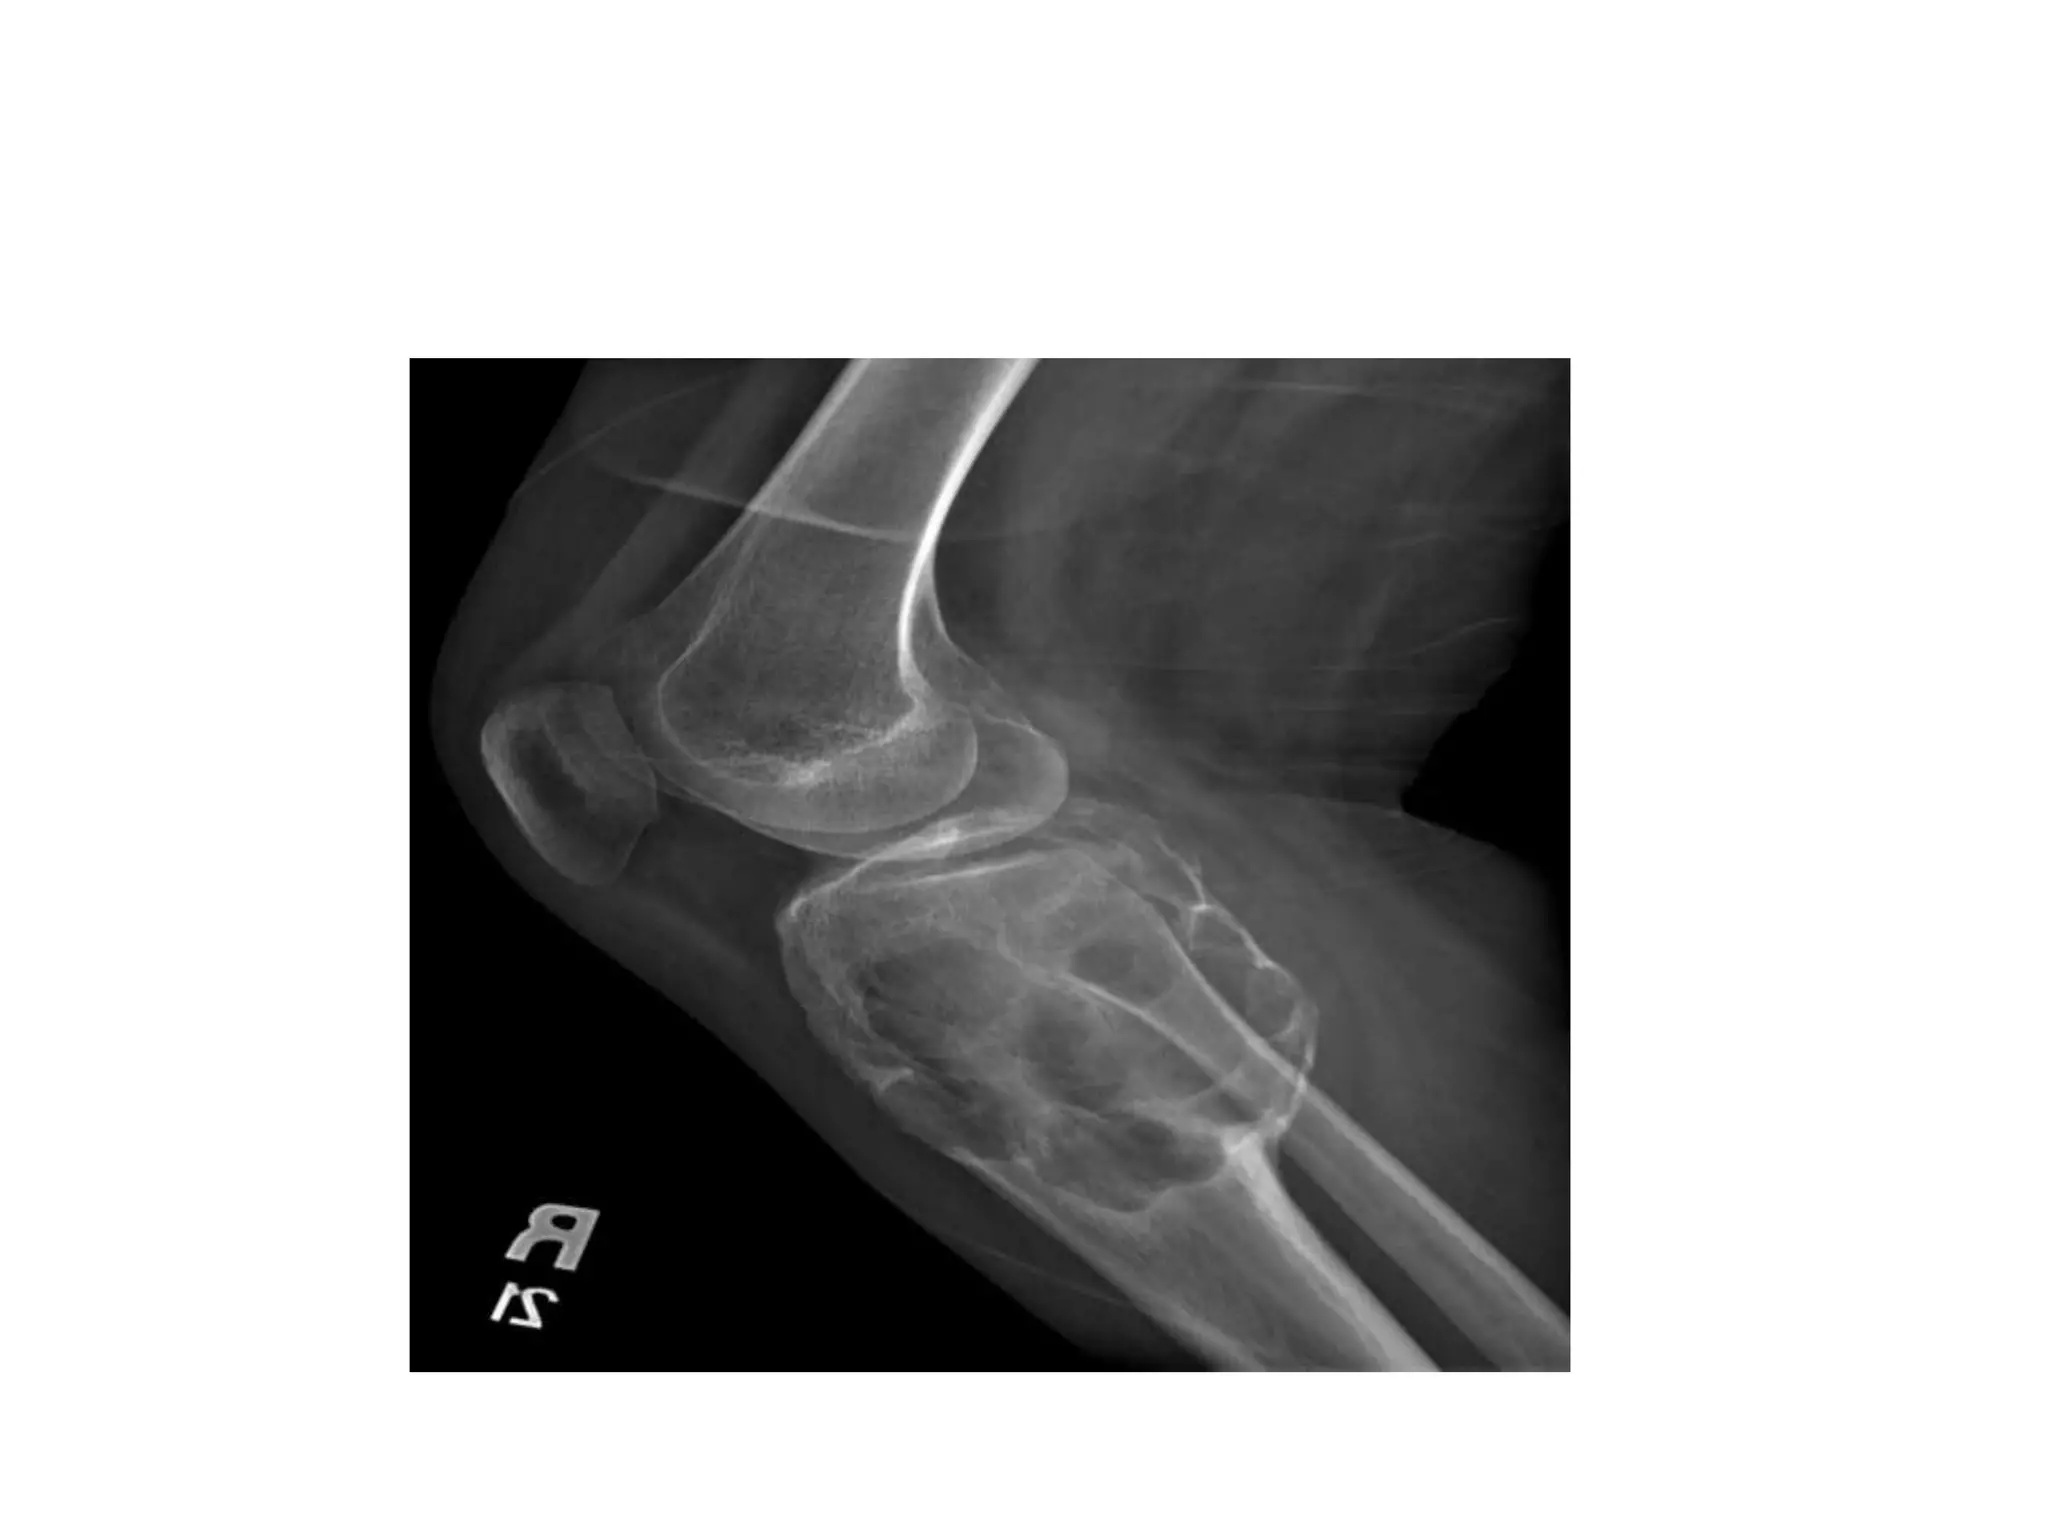

Osteochondroma

• Solitary Osteochondroma

• Multiple Hereditary Exostoses

• Malignant transformation may occur

• Treatment : osteochondromas may

spontaneously regress. They are usually treated

by simple excision for cosmetic reasons or

when symptoms of pain, limitation of motion,

or impingement on adjacent structures such as

nerves and blood vessels become clinically

manifest.